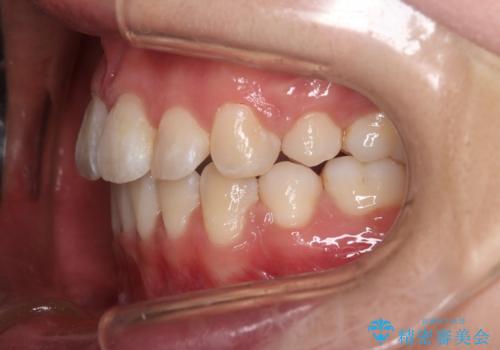

抜歯矯正をして口元を下げたことで、口元が下がりEラインが大変綺麗になりました。

矯正期間も1年9ヶ月と比較的短期間で終了することができました。